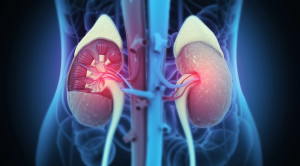

Stepwise Incremental Hemodialysis and Low-Protein Diet Supplemented with Keto-Analogues Preserve Residual Kidney Function: A Randomized Controlled Trial Kittiskulnam P, Tiranathanagul K, Susantitaphong...(Baca Selengkapnya)